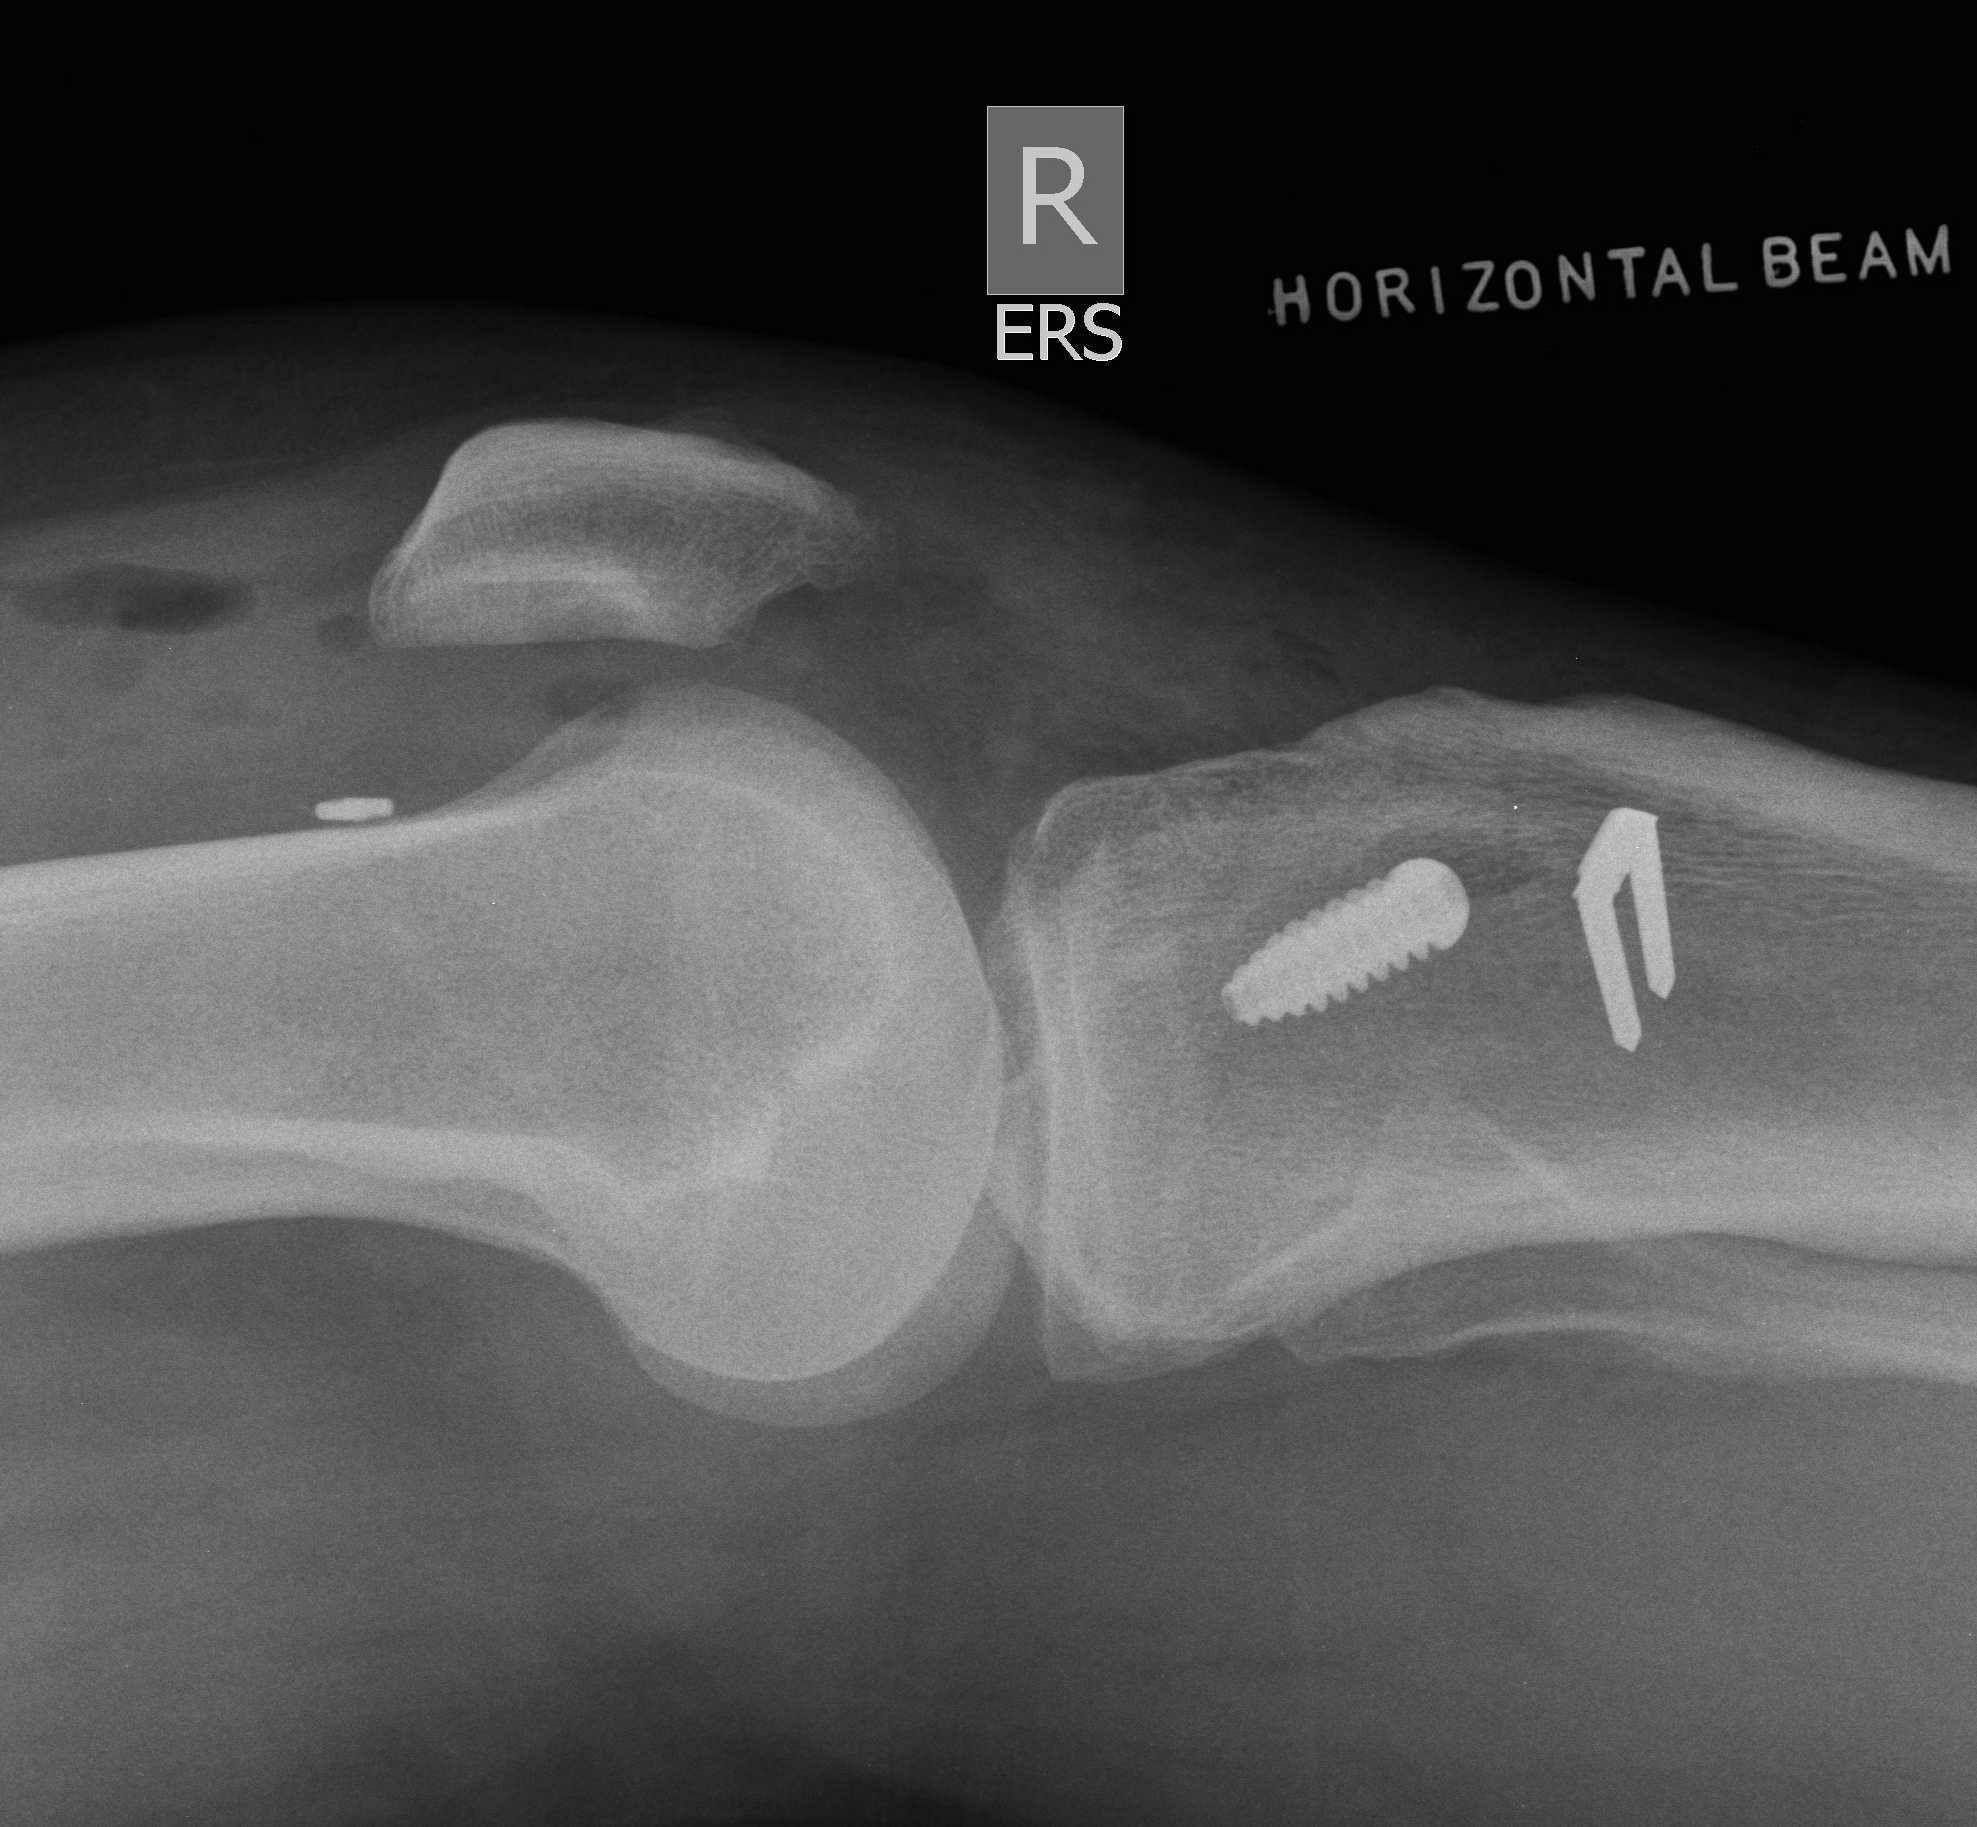

Femoral Tunnel Drilling

- pass 4.5mm endobutton drill completely through femoral cortex

- remove beath pin and insert depth gauge

- measure femoral tunnel (between 34 and 46 mm)

- drill appropriate sized tunnel with acorn reamer to within 10mm of cortex (for 20 mm endobutton)

- gives room to pull through and flip 10 mm endobutton

- if 15 mm endobutton need to be within 5 - 7 mm

- carefully clean out all bone fragments with shaver / depth gauge or may prevent graft passage

- insert loop 1 nylon to pass graft later

Tibial fixation

Place beath wire and pass RCI screw anteriorly

- usually 8 or 9 mm for men and women

- the tibial bone is soft

- will usually take a 25 mm screw / up to 35 mm

- +/- supplemental post / screw / staple